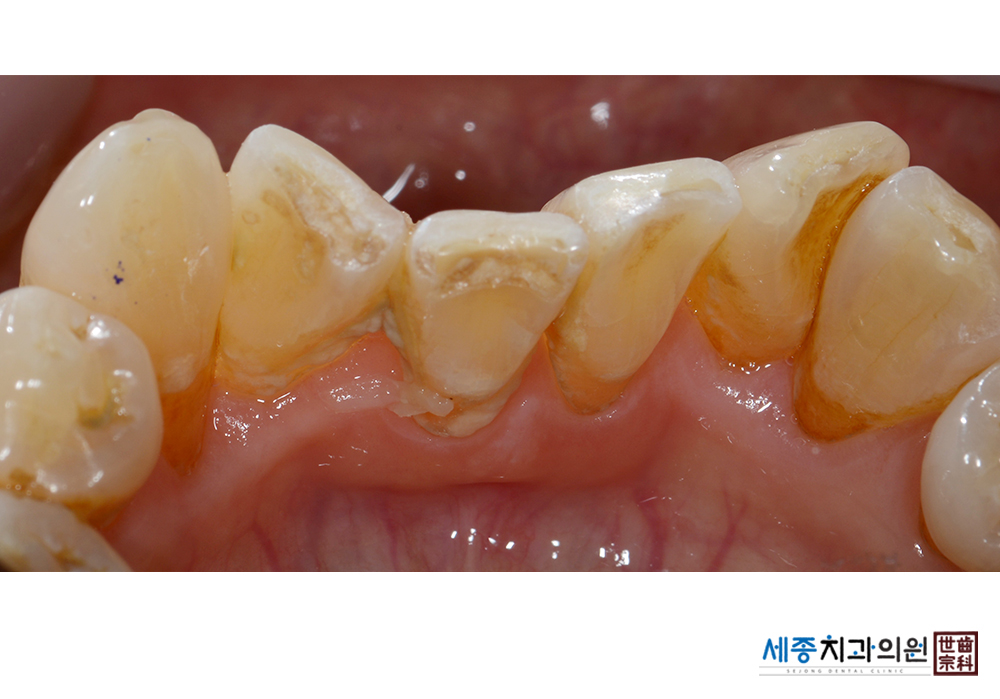

[스케일링] 치주질환 예방 스케일링

치료후 : 2019-09-24

가글마취&저주파 스켈러를 사용한 스케일링